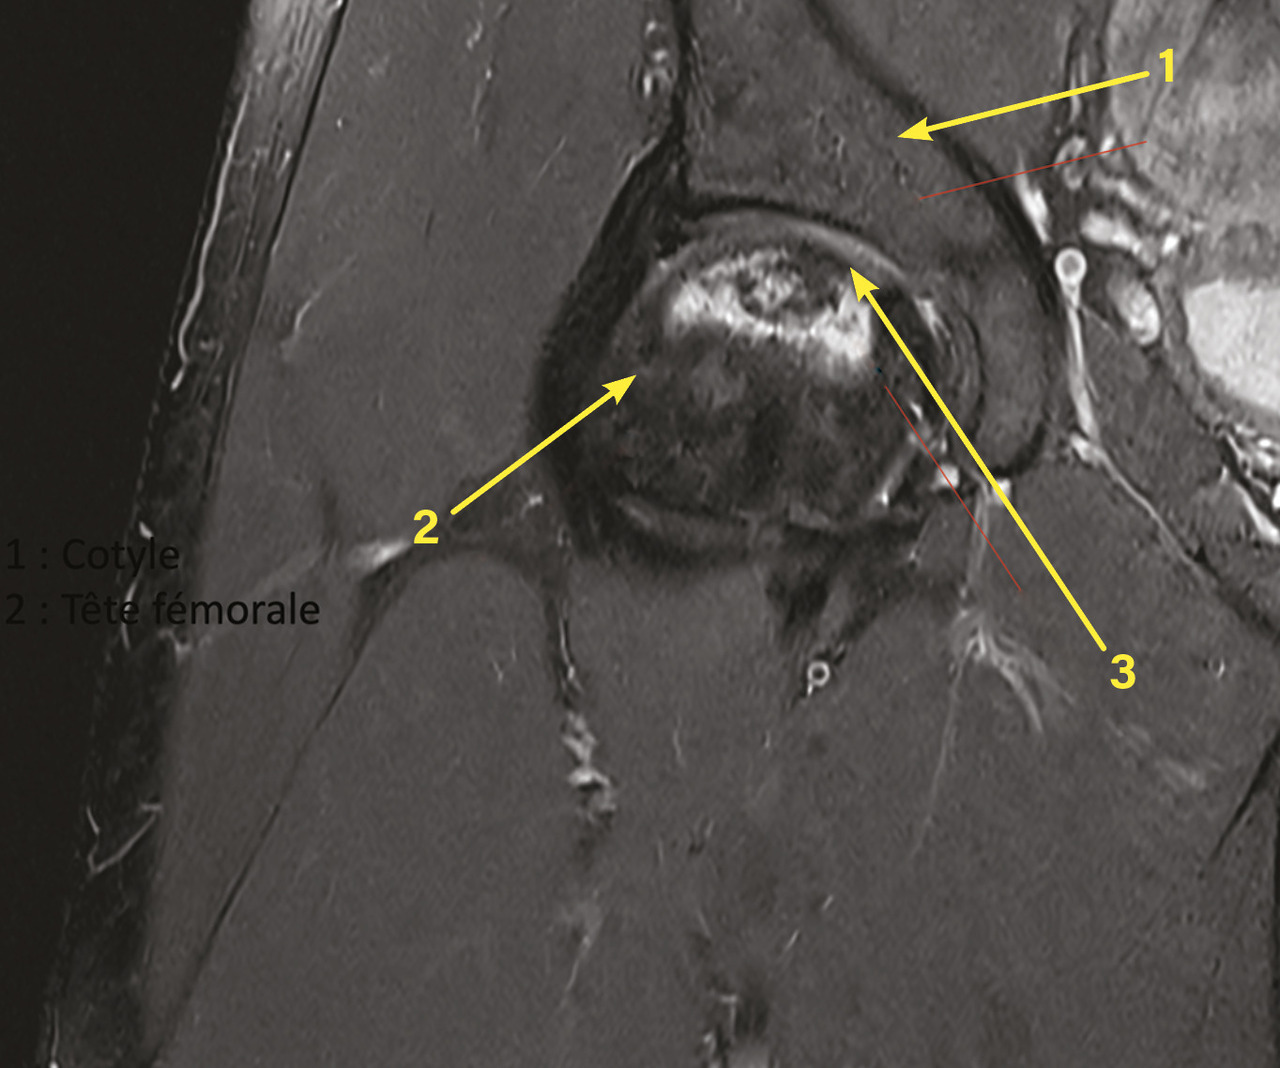

À l’interrogatoire, le patient ne présente pas de facteur de risque. Son examen clinique n’objective pas de limitation des amplitudes articulaires avec un testing musculaire normal. Il est adressé à un chirurgien orthopédique qui, après un bilan radiologique d’extension, propose une prise en charge par surveillance simple avec risque important de dégradation dans les années à venir, ou chirurgicale conservatrice par forage, greffe avec éviction de l’appui, pour une durée de six semaines. Cette dernière solution est choisie par le patient (fig. 1 ). Le contrôle (IRM) six semaines après l’opération ne montre pas de progression de la maladie, la greffe spongieuse réalisée est toujours présente (fig. 2 ).

À l’interrogatoire, le patient ne présente pas de facteur de risque. Son examen clinique n’objective pas de limitation des amplitudes articulaires avec un testing musculaire normal. Il est adressé à un chirurgien orthopédique qui, après un bilan radiologique d’extension, propose une prise en charge par surveillance simple avec risque important de dégradation dans les années à venir, ou chirurgicale conservatrice par forage, greffe avec éviction de l’appui, pour une durée de six semaines. Cette dernière solution est choisie par le patient (